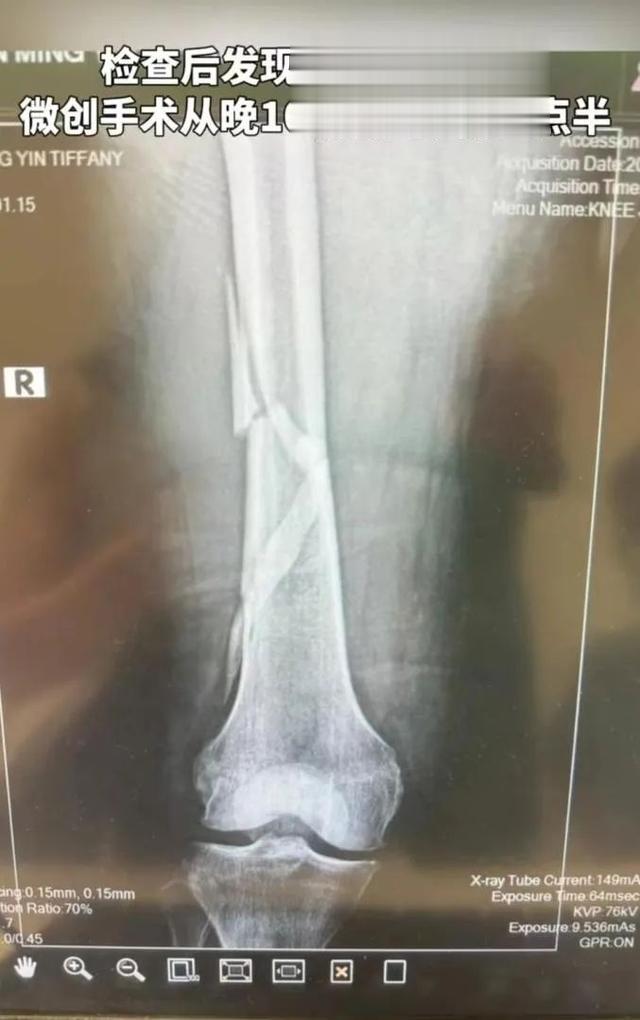

演员陈哲远在除夕夜

洗澡时不慎摔倒

导致骨折

此前 , 向太陈岚

也在短视频平台上发文

自己在浴室洗澡时

在刚好没有防滑垫的地方摔倒了

导致大腿骨断裂

手术持续5个半小时